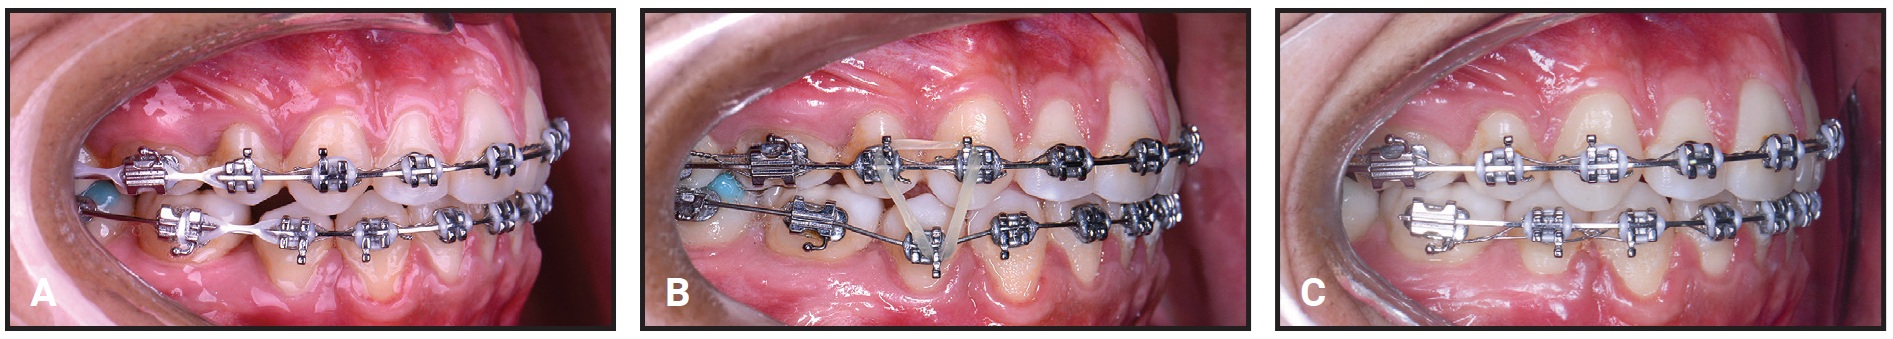

In this case, I was attempting to pull the molars for three months to no avail (Fig. 12A). A progress photograph finally made me realize that I was being stubborn in trying to close a space that wasn’t going to close, because the problem was vertical and not mesiodistal. To overcome this mistake, I repositioned the first-premolar bracket gingivally and extruded the tooth with an .016" nickel titanium archwire and 3/16" vertical intermaxillary elastics (Fig. 12B). The premolar was large enough to close the remaining space (Fig. 12C).

Fig. 12 A. Lower-molar space remaining after second-premolar extraction and three months of treatment. B. After gingival bracket repositioning, first premolar extruded using .016" nickel titanium archwire and 3/16" vertical intermaxillary elastic. C. Space finally closed, and .018" × .025" stainless steel lower archwire inserted with .010" ligature wire for stabilization.